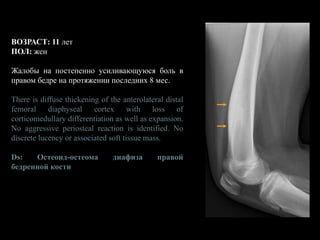

ВОЗРАСТ: 11 лет

ПОЛ: жен

Жалобы на постепенно усиливающуюся боль в

правом бедре на протяжении последних 8 мес.

There is diffuse thickening of the anterolateral distal

femoral diaphyseal cortex with loss of

corticomedullary differentiation as well as expansion.

No aggressive periosteal reaction is identified. No

discrete lucency or associated soft tissue mass.

Ds: Остеоид-остеома диафиза правой

бедренной кости